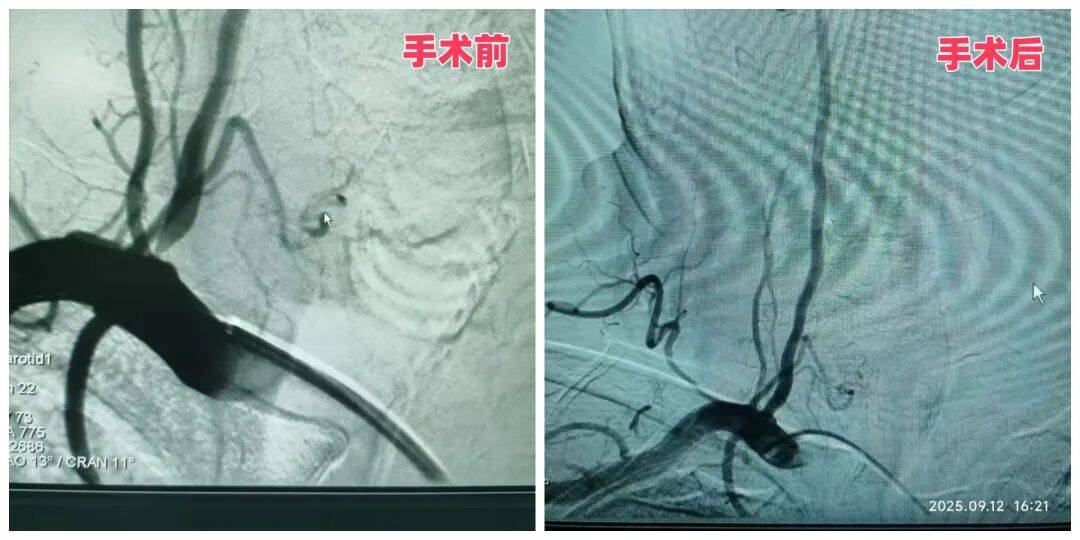

57岁的李大哥半年内因反复头晕住院三次,出现两次右侧小脑急性梗死,经检查确诊为“双侧椎动脉起始段狭窄”,其中右侧已达重度狭窄,随时可能再次引发脑梗。神经内科二病区主任袁秀琴、主管医生杨伟伟、护士长马晓玲结合患者的高血压、糖尿病病史及既往脑梗情况,术前为患者进行降压、降糖治疗,并制定了 “主动脉弓 + 脑血管造影术 + 右侧椎动脉支架植入” 的精准治疗方案。

手术中,医生凭借丰富的介入经验,将支架精准植入右侧椎动脉狭窄处,成功撑开狭窄血管。术后复查患者右椎动脉供血恢复正常。这例手术的成功,标志着科室在脑血管狭窄精准治疗领域的技术已趋于成熟,能为复杂病情患者提供安全有效的方案。